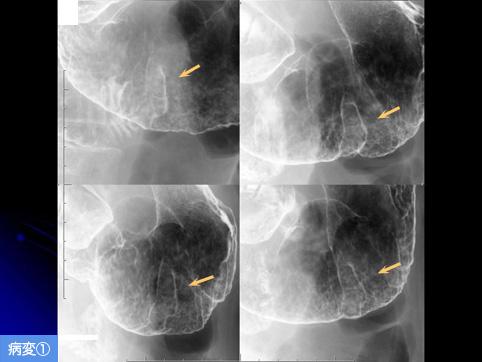

疾病(病理主体)的分类良性上皮性肿瘤/腺瘤

部位(按器官分)胃(部位)/前庭

检查方法X线

肿瘤的肉眼分类0型(表在型)/IIa型(IIa)

肿瘤最大直径20~24

多发性肿瘤(同一器官)有(同时性)